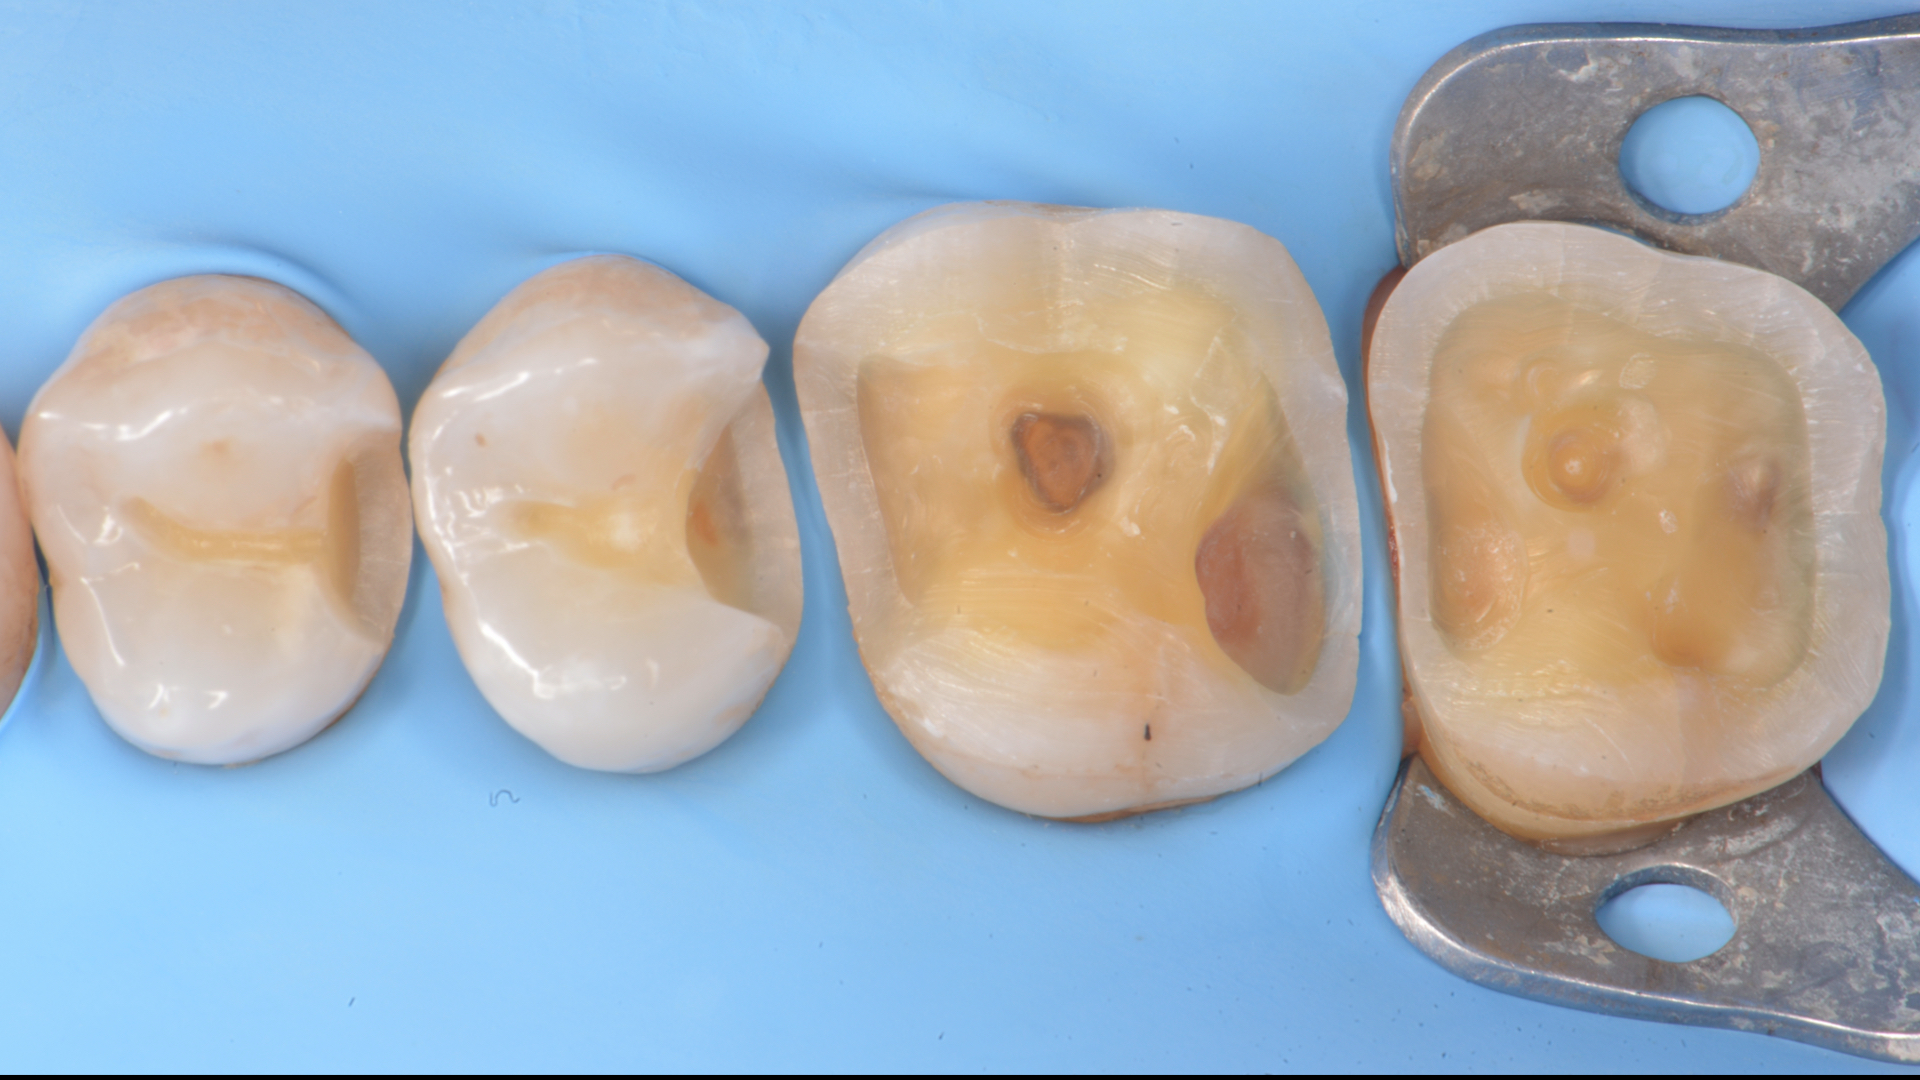

Il paziente si è presentato alla nostra osservazione lamentando fastidi in masticazione e sensibilità termica nell’arcata superiore destra.  Dopo  esame  clinico  e  radiografico  si  sono  evidenziate lesioni cariose a carico degli elementi 1.7-1.6-1.5.-1.4 Si è optato per un restauro diretto in composito con approcci minimamente invasivo negli elementi 1.4 ed 1.5 . A carico degli elementi 1.7 e 1.6 sono stati invece programmati restauri indiretti in composito ibrido a ricopertura cuspidale. Questa scelta è stata presa dopo una accurata valutazione biomeccanica delle strutture residue.

Dopo  avere  eseguito  i  restauri diretti tramite l’utilizzo del sistema sezionale  Garrison  Composi-tight 3D Fusion sono stati preparati gli elementi  1.7  e  1.6.  L’impronta  è stata rilevata con tecnica monofase bicomponente.  Al  successivo appuntamento, previo isolamento del  campo  operatorio  con  diga di  gomma,  i  manufatti  sono stati  cementati  con  composito preriscaldato.  In  questo  caso l’utilizzo  di  tale  composito  ha facilitato  le  fasi  di  rimozione  del cemento in eccesso a causa della diversa opacità tra prima e dopo la polimerizzazione . Fasi di rifinitura,lucidatura e brillantura sono state eseguite  prima  della  rimozione della  diga.  Minimi  aggiustamenti occlusali sono stati necessari.

9

10

Fig.9 Cavità pulite e sabbiate prima della cementazione)Fig.10 Cementazione del manufatto elemento 1.7 con composito preriscaldato